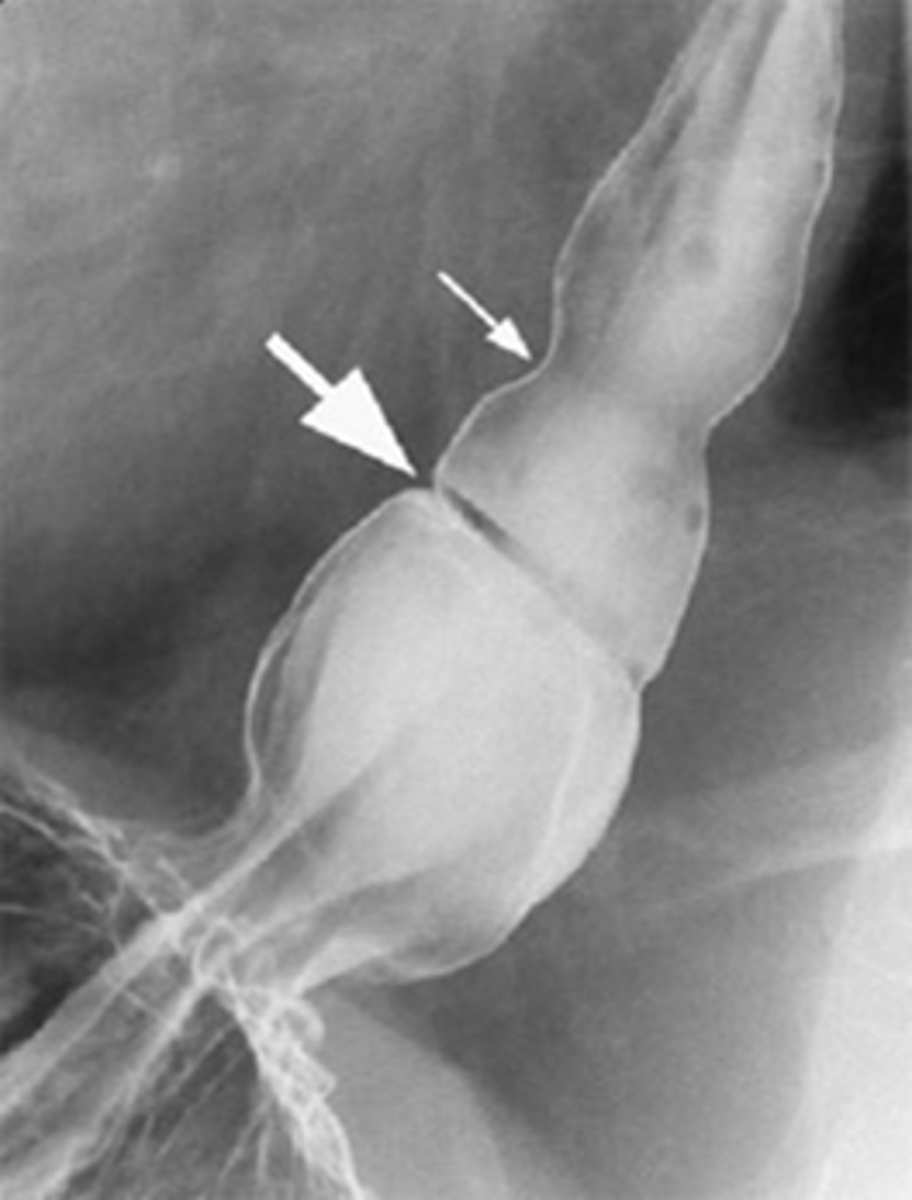

Cricopharyngeal achalasia/Zenker's diverticulum

rare clinical entity in which upper esophageal sphincter (cricopharyngeus) does not open adequately during swallowing leading to dysphagia.

Diverticulum of the mucosa of the pharynx just above the cricopharyngeal muscle.

Zenker's diverticulum

Upper right hiatal hernia with schatzki's ring

THICK WHITE ARROW: Schatzki's ring

THING WHITE ARROW: stricture